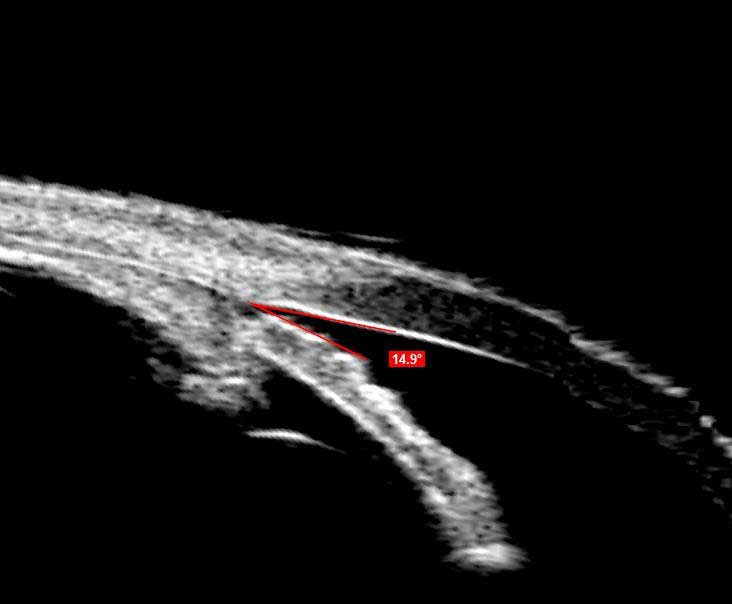

UBM

UBM незамінний при візуалізації переднього відрізка ока. Зображення з високою роздільною здатністю UBM дають можливість спостерігати структури, приховані райдужною оболонкою або помутніннями рогівки.

Програмне забезпечення Scanmate надає інструменти для вимірювання кутів, площі та довжини, а також інструмент анотації для позначення патологій. Наповнений водою одноразовий стерильний чохол Clear Scan® Probe є єдиним компонентом, який торкається ока.

UBM зонд застосовується для: Вимірювання ACA; Оцінки рогівки після LASIK; Моніторингу положення ІОЛ; Передопераційної оцінки ICL; Діагностики кіст райдужки та циліарної оболонки; Післяопераційного обстеження глаукоми.